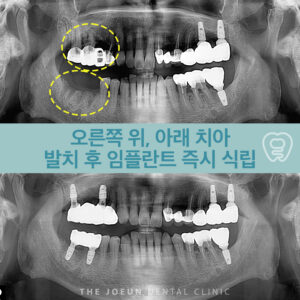

달서구임플란트잘하는곳 치조정 접근법을 통한 상악동 뼈이식술 임플란트는 치아가 빠진 부위에 티타늄으로 만들어진 인공치근을 치조골에 식립하여 상부에는 크라운을 제적하여 연결하는 보철치료르 말합니다. 치아의 뿌리부터 머리까지 자연치와 비슷한 모양으로 심미성이 뛰어나고, 자연치와 유사한 기능을 보이는데요. 이는 잇몸뼈에 식립체를 직접 식립하게 되는데 진행을 위해서는 치조골의 양과 상태가 충분해야 합니다. 치아를 상실했어도 치조골 상태가 더보기…